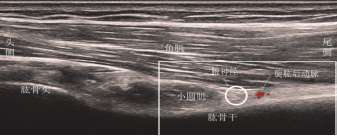

AN前路超聲解剖學特點(圖1):

使用能顯示小神經的行動式高頻線陣超聲探頭掃描,將超聲探頭橫向放置在胸大肌的外側邊緣處,臂外展以識別腋窩中的臂叢神經,短軸平面顯示臂叢位於背闊肌和背闊肌肌腱前面。 將探頭稍微向頭側移動,一旦大圓肌的上邊緣消失即可確認QS。QS是肱骨和大圓肌之間的狹窄間隙,其中AN表現為伴有PCHA的高回聲蜂窩狀橢圓形結構。 PCHA的起源和走行變化很大,僅作為識別AN的輔助結構之一。進入QS或在肩胛下肌之前,可以看到AN。手臂從90°外展180°使神經透過關閉QS更緊密貼近面板。